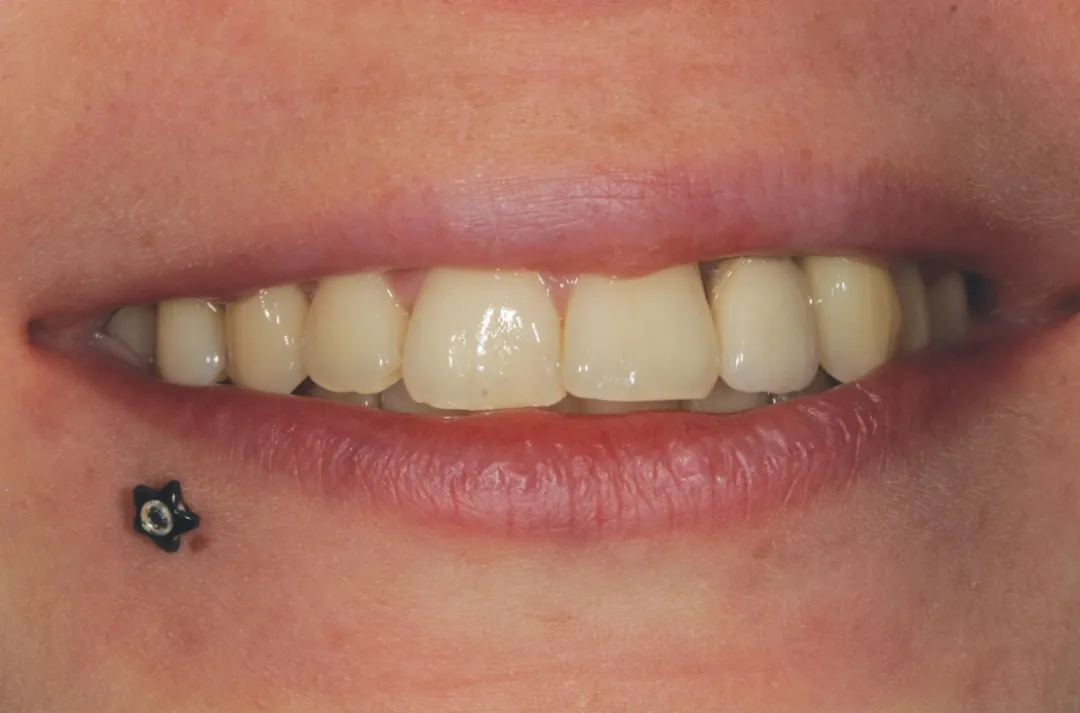

图 33 :最终完成,自然微笑。

图 34 :挤压安装最终修复体。

图 35 :术后 1 年随访 X 线影像。